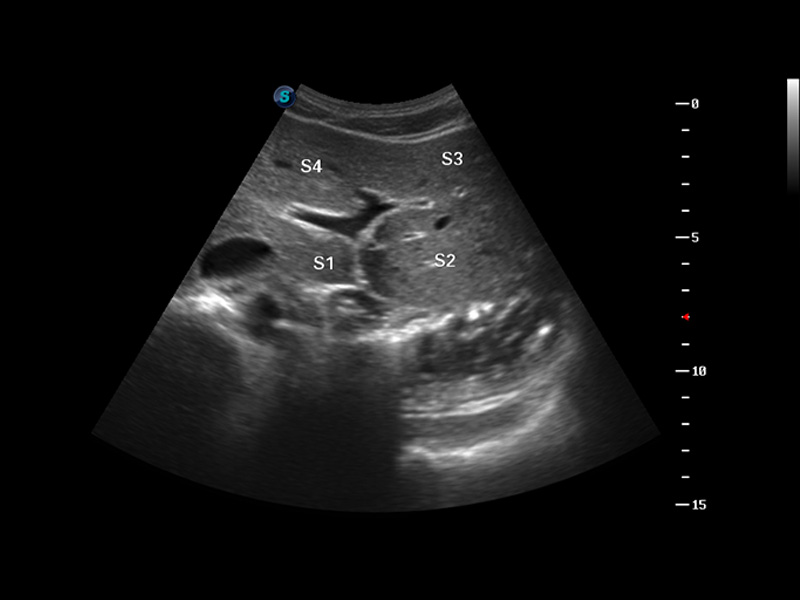

肝脏